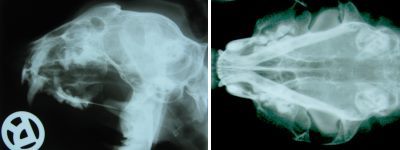

• Zahnröntgen

Zahnröntgen Katze